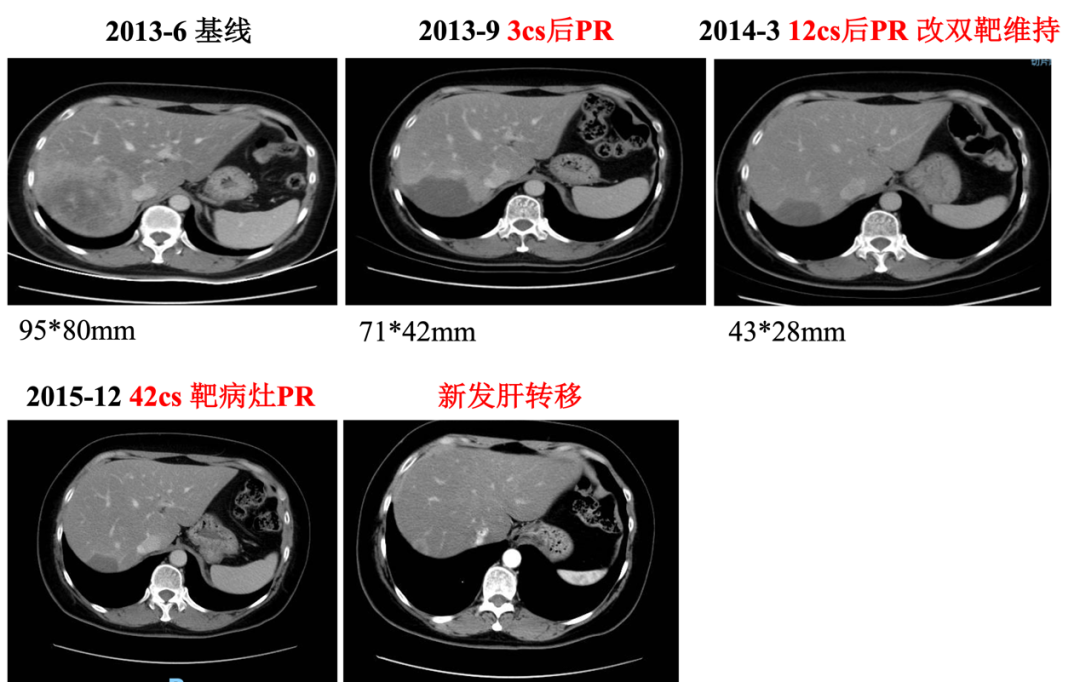

入组MO28047临床试验(PERUSE研究),于2013-7-16开始行紫杉醇+曲妥珠单抗+帕妥珠单抗方案治疗,具体:紫杉醇175mg/m2 270mg d1;帕妥珠单抗首剂840mg,以后420mg d1;曲妥珠单抗首剂 8mg/kg 484mg,以后6mg/kg 363mg d1,Q21d。最佳疗效PR,自第10周期调整为双靶维持治疗。2015年12月(42周期时)原靶病灶维持PR,新发18mm肝转移,评效病情进展,PFS为30月。不良反应:腹泻2级,粒细胞下降2级。

图2. 一线治疗